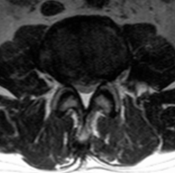

没有一种检查可以诊断腰椎间盘突出症。医生对患者进行详细的病史采集和临床体格检查后,要结合相关检查结果,综合进行诊断。CT检查显示椎间盘突出的部位、大小、形态和神经根、硬脊膜囊受压移位的形象,同时可显示椎板及黄韧带肥厚、小关节增生肥大、椎管及侧隐窝狭窄等情况,并可以三维技术重建椎管与根管的立体形态。此外,用水溶性造影剂做脊髓造影与CT检查结合,能提高诊断的准确性。MRI检查对椎间盘突出症的诊断具有重要意义。通过不同层面的矢状面影像及所累及椎间盘的多方位影像,可以观察病变椎间盘突出的形态及其与周围组织的关系。对于不能行MRI检查患者,也可以进行脊髓造影检查,准确性也很高。

腰椎X片、CT、MRI检查各有优缺点,具有互补性。患者患了腰椎间盘突出到医院就诊首先会行 X线片检查,可排除其它骨性病变。对于腰椎间盘突出症患者怀疑有骨质异常(狭部裂,骨骺离断)时考虑行CT检查。核磁共振成像技术(即MRI)是对于软组织(椎间盘突出部位,方向,脊髓神经根受压情况)检查方法,除了临床病史和体格检查,MRI已经是诊断腰椎间盘突出症的常用检查方法。